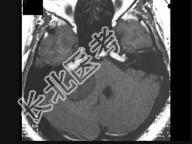

- 单项选择题男,44岁, 右耳听力进行性减弱,结合图像, 最可能的诊断为 ( )

A、听神经纤维瘤

B、三叉神经鞘瘤

C、前庭神经鞘瘤

D、胆脂瘤

E、脑膜瘤